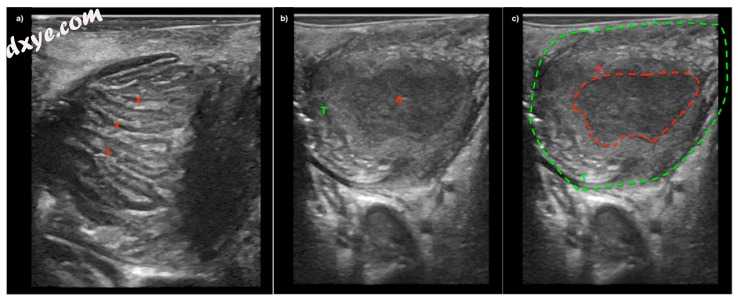

4.jpg

图4

图像(a)患有严重扁桃体炎的患者,伴有扁桃体周围肿胀。 超声波可见扁桃体肥大,发炎的扁桃体隐窝(x)但没有脓肿。 图(b)和(c)来自另一名患者的超声图像,显示具有脓肿腔的腭扁桃体(T)(A)。 所有成像均使用Hockey Stick换能器和GE Logiq S7超声系统(GE_Healthcare Chicago,Chicago,IL,USA)捕获。